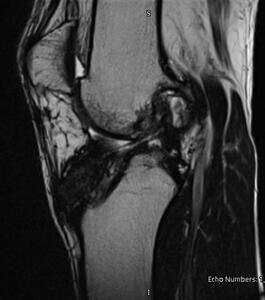

A healthy 22-year-old male presented with anterior left knee pain after noting a popping sensation that started a month prior after falling awkwardly and twisting his knee. Examination revealed near full range of motion with an increase in laxity on Lachman’s exam compared to the right. Magnetic resonance imaging (MRI) demonstrated a complete tear of the left ACL with a concomitant tear involving the posterior root of the medial meniscus (Fig. 1). He subsequently underwent primary left ACL reconstruction with TAT allograft and a partial medial meniscectomy. The choice of graft was left up to the patient and residual knee/harvest pain was the reason for choosing an allograft option instead of harvesting an autograft. This was performed in standard fashion with anterior medial and anterior lateral arthroscopic portals. The posterior root of the medial meniscus was stable with partial fraying present, therefore debridement with an arthroscopic shaver was utilized. The Arthrex system was used with a flip cutter for the femur (25 mm tunnel length) and a standard reamer for the tibia based on the size of the graft. The TAT allograft was then prepped in standard fashion and passed while the button was flipped on the femur. The knee was then cycled with tension applied to the sutures and an interference screw was inserted into the tibial tunnel in a retrograde fashion. Postoperatively, the patient was allowed to weight-bear right away in a hinged knee brace, limiting motion from full extension to 30 degrees of flexion for the first 2 weeks and progressively working up to full range of motion by 6 weeks. Two months later the patient’s pain had improved with appropriate weakness in the left knee (4/5 strength in knee flexion/extension) and a firm endpoint during Lachman’s test. Approximately seven months postoperatively, the patient returned, complaining of significant left knee pain after falling from a rebound attempt while playing basketball. Repeat MRI at this time demonstrated a complete mid substance tear of the left ACL graft and an associated lateral meniscus tear (Fig. 2). The patient underwent a revision left ACL reconstruction with an Artelon bio-scaffold for augmentation of a TAT allograft. The revision procedure was performed in standard fashion as described above during the index procedure in addition to interlocking an Artelon bio-scaffold within the stitching of the TAT allograft using monofilament absorbable suture (Figure 4, Figure 5). Postoperative mobilization and range of motion restrictions were employed the same as before following the index procedure. Physical therapy began shortly after surgery, and he slowly regained motion and strength in the left knee. Six weeks postoperatively, the patient was pain-free and doing well, consistently attending physical therapy appointments. On examination, there was a firm endpoint during Lachman’s test of the left knee and 4/5 strength in knee flexion and extension. At 24 months postoperatively, the patient admitted full strength (5/5 strength in knee flexion/extension) and range of motion (0-120 degrees) along with a stable left knee without symptoms of pain or instability with stairs or quick-cutting movements. He also regained the ability to run brace-free again without worry. No reoperations or complications were noted in the left knee following the revision procedure and the patient noted significant satisfaction with the ability to perform activities similar to his pre-injury level.